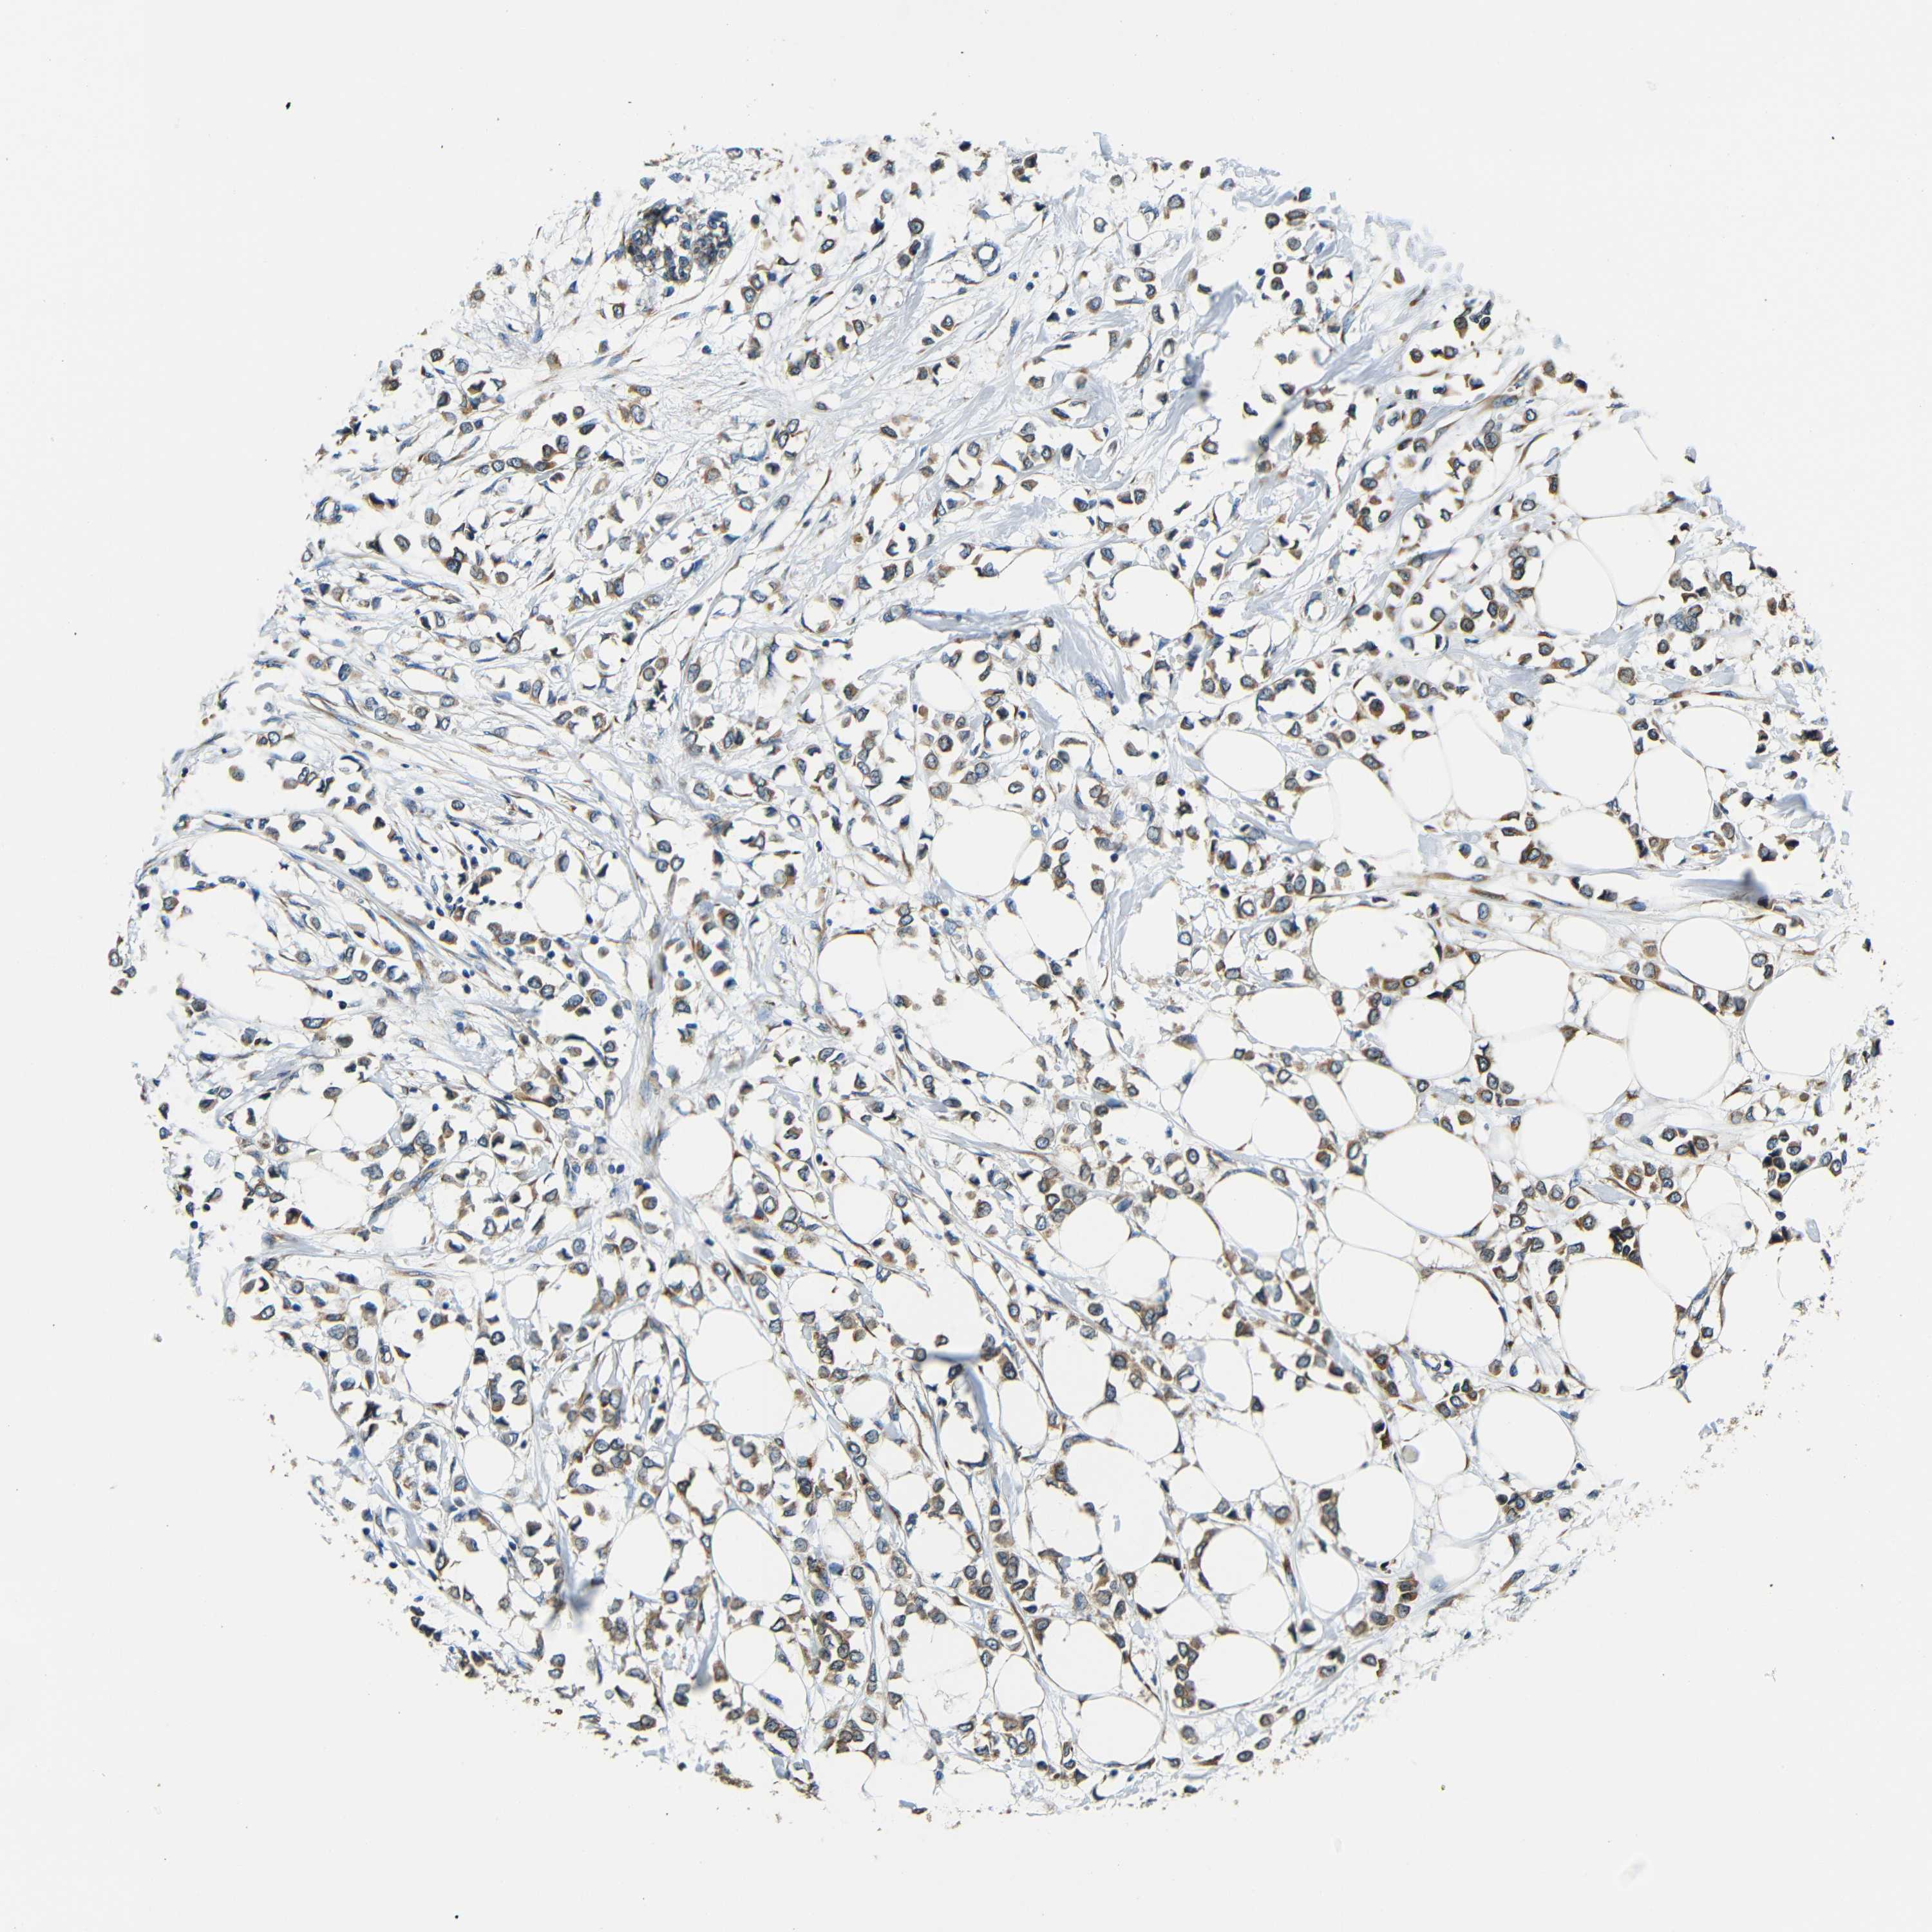

Breast cancer

Human cancer